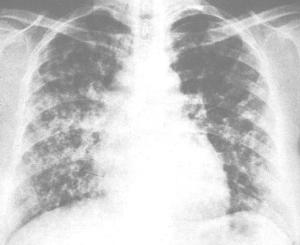

小儿呼吸道合胞病毒肺炎(RSV)简称合胞病毒肺炎,是一种小儿常见的间质性肺炎,多发生于婴幼儿。由于母传抗体不能预防感染的发生,因而出生不久的小婴儿即可发病,有报道新生儿病毒性肺炎中RSV占10%~15%,国外偶有院内感染导致产科医院新生儿病房暴发流行的报道。